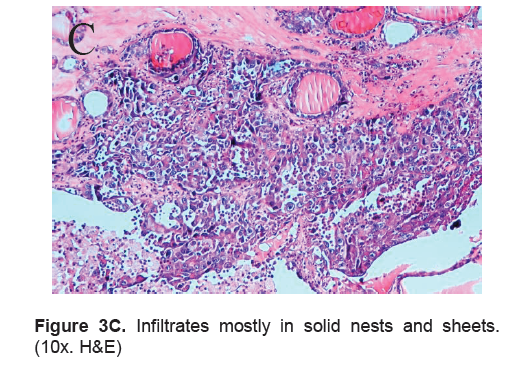

The right lobe measured 8.3 x 6.0 x 4.3 cm, and weighed 119.5 grams with a tan brown surface covered with fibrous tags (Figure 3A). Cut sections showed an ovoid mass, 6.7 x 5.2 cm in greatest dimensions, with a thin capsule and yellow-tan, gritty to mucoid cut surface with areas of hemorrhage and necrosis. The tumor infiltrated and replaced normal thyroid parenchyma and was surrounded by a thin capsular rim. Tissue sections of the right lobe revealed an infiltrative tumor composed of an admixture of pleomorphic cells, spindle cells and occasional tumor giant cells (Figure 3B). There were small areas showing reminiscent papillary or microfollicle pattern, while some areas showed large epithelioid or multinucleated tumor cells with bizarre nuclei (Figure 3C). Capsular (Figure 3D) and vascular (Figure 3F) invasion were present with extensive tumor necrosis. The uninvolved right and left lobes showed multinodular colloid goiter with lymphocytic thyroiditis. It was signed out as an Anaplastic (undifferentiated) thyroid carcinoma of the right lobe.

Click here to download Figure 3C

Figure 3C. Infiltrates mostly in solid nests and sheets. (10x. H&E)